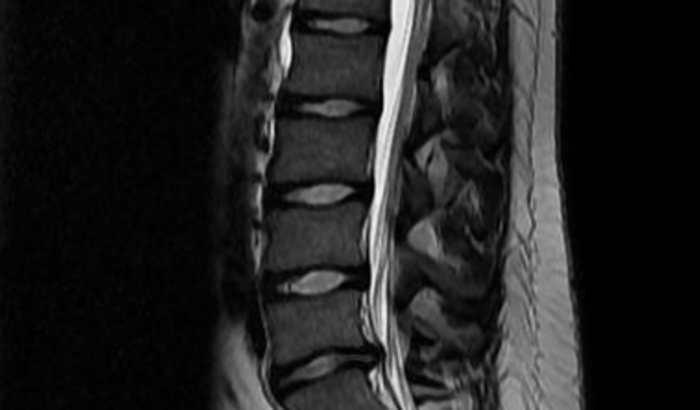

Oi gente, tudo bem? Preciso da ajuda de vocês. Estou enfrentando uma desnervação/degeneração dos nervos, do lado esquerdo da coluna, por conta de uma hérnia e preciso fazer a retirada do disco que se encontra rompido. No momento estou tendo crises corporais, onde não consigo mover nem sentir minhas pernas por algumas horas, o que me impede totalmente de trabalhar. A cirurgia sairá pelo valor de 13.200,00 R$, mas parte desse valor já foi arrecadado. Preciso ainda, no total, de 7.000 R$ para fazer essa cirurgia. Se você quiser e puder me ajudar, qualquer quantia é bem-vinda. Não há um valor mínimo estipulado e qualquer valor será crucial para a realização desse processo cirúrgico. Caso você tenha alguma dúvida sobre a doação ou sobre a própria cirurgia, fique a vontade para perguntar no meu perfil do instagram. Desde já agradeço de coração a tua ajuda, seja contribuindo ou ao menos compartilhando essa postagem. Link do instagram: @_romuloalmeida_